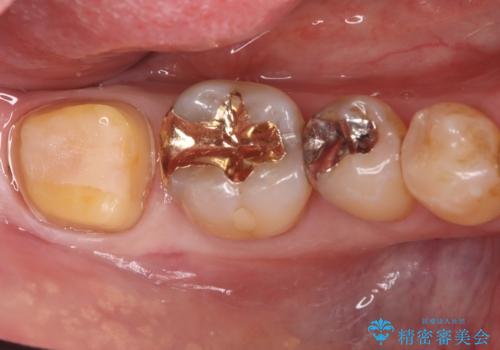

治療ではまず、欠けた部分を修復し、歯全体を均一に形成しました。その後、PGA(白金加金)クラウンを作製・装着しました。

PGAクラウンは、金(Gold)を主成分とする合金でできており、非常に優れた特性を持っています。

強度: 非常に高い強度を持つため、奥歯の強い咬合力にも耐え、歯の破折を効果的に防ぎます。

適合性: 歯への適合性が非常に高く、精密に隙間なく装着できるため、被せ物の下からの二次的な虫歯のリスクを最小限に抑えられます。

この治療により、欠けてしまった歯の構造的な弱点が解消され、患者様は硬いものでもしっかりと噛める、安心で機能的な奥歯を取り戻すことができました。